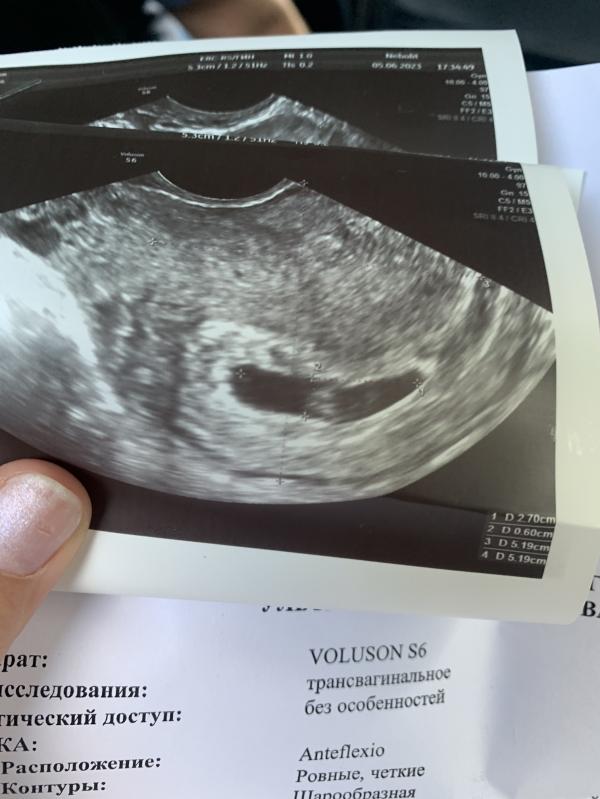

УЗИ показало только формирование эмбриона: что делать, если эмбриона не видно?

Девочки сходила на Узи сегодня,не могла терпеть долго😃

Съездила в платную,смотрел мужчина.

Эмбриона он не увидел,но увидел как идет только формирование эмбриона.Трубку увидел😌